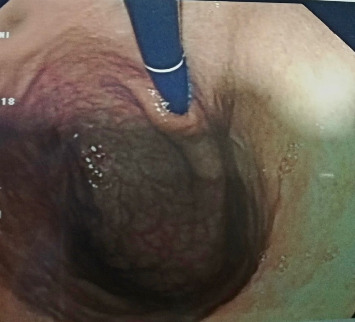

behet病(BD)是一种引起口腔溃疡、生殖器溃疡、眼睛炎症和皮肤病变的全身性炎症。自身炎症和自身免疫性疾病是导致组织炎症的慢性免疫系统激活。目前的证据表明,双相障碍是自身免疫综合征和自身炎症综合征的交叉点,一些研究结果表明其具有自身炎症的性质。口腔溃疡是该疾病最常见的初始表现。胃症状在BD中并不常见。胃溃疡或胃炎通常表现为胃脘痛。双相障碍与几种自身免疫性疾病有关;然而,在自身免疫性萎缩性胃炎中尚未发现。我们报告一位62岁男性病患,以口腔阿弗顿溃疡为主诉,并伴有腹痛、上腹部不适及餐后恶心。患者HLA-B5等位基因呈阳性,诊断为BD。胃镜和结肠镜检查了该患者胃脘不适和腹痛的可能病因。胃镜检查显示眼底多处糜烂,胃体处有萎缩褶皱,结肠镜检查未见重要发现。此外,胃活检证实在胃底和胃窦水平存在自身免疫性萎缩性胃炎,这在BD中是不典型的,通常与回肠末端水平的阿佛氏溃疡有关。据我们所知,这是第一例报道,这应该促使我们进一步调查这两种疾病之间的联系机制。

Behçet's disease (BD) is a systemic inflammatory condition causing oral ulcers, genital sores, eye inflammation, and skin lesions. Autoinflammatory and autoimmune disorders are chronic immune system activation leading to tissue inflammation. Current evidence suggests that BD is at the intersection of autoimmune and autoinflammatory syndromes, with some findings suggesting an autoinflammatory nature. Oral aphthous ulcers are the commonest initial manifestation of the disease. Gastric manifestations in BD are infrequent. The usually seen finding in the stomach is either ulcers or gastritis, presenting as epigastric pain. BD has been linked with several autoimmune diseases; however, it has not yet been seen with autoimmune atrophic gastritis. We present a case of a 62-years-old male patient presenting for oral aphthous ulcers with vague abdominal pain, epigastric discomfort, and postprandial nausea. The patient was positive for HLA-B5 alleles, leading to a diagnosis of BD. Gastroscopy and colonoscopy were done to investigate a probable etiology for this patient's epigastric discomfort and abdominal pain. Gastroscopy showed multiple erosions at the level of the fundus and atrophic folds at the level of the body of the stomach, but no important findings were seen on colonoscopy. Furthermore, a gastric biopsy was done and confirmed the presence of autoimmune atrophic gastritis at the level of the fundus and antrum of the stomach which is atypical in BD that is commonly associated with aphthous ulcerations at the level of the terminal ileum. To our knowledge, this is the first case reported, which should prompt for further investigation behind the mechanism linking these two diseases.